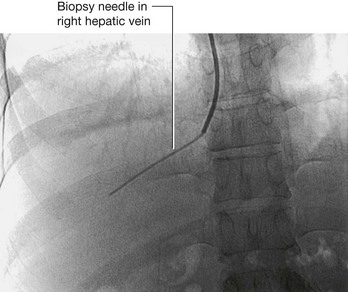

Transitional cell carcinoma arises from the urothelium. The urothelium is present from the calices to the urethra and behaves as a “single unit.” Therefore, when patients develop transitional carcinomas within the bladder, similar tumors may also be present within upper parts of the urinary tract. In patients with bladder cancer, the whole of the urinary tract must always be investigated to exclude the possibility of other tumors (Fig. 4.144).

image

Fig. 4.144 Transitional cell carcinoma in the pelvis of the right kidney. Coronal computed tomogram reconstruction.